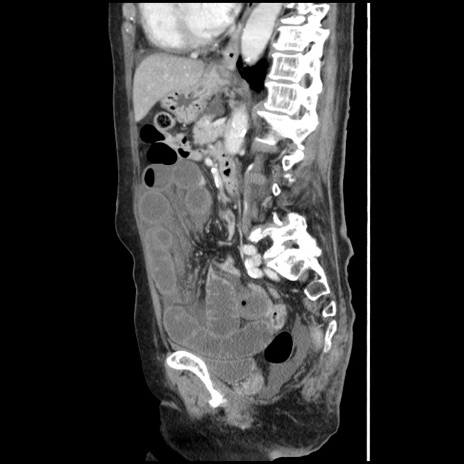

冠状断像

【症例】80歳代女性

【主訴】腹痛

【現病歴】8時間前から腹痛あり来院。

【既往歴】糖尿病、脂質異常症、子宮体癌にて子宮全摘術

【身体所見】意識清明・会話良好だが腹痛で苦悶様、全腹部にわたって反跳痛と圧痛あり

【データ】WBC 13600、CRP 0.14、LDH 224、CK 90